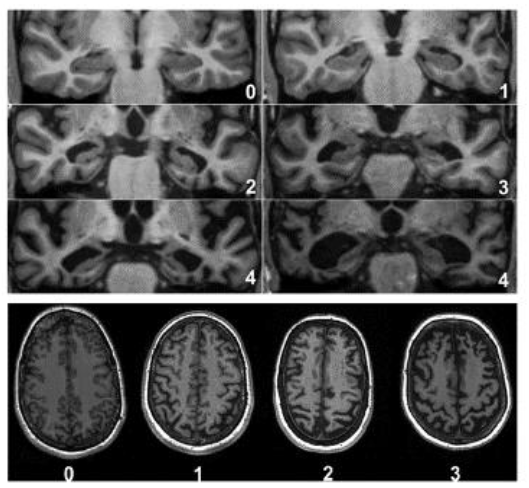

根據研究指出,在阿茲海默症發病之前的臨床前期及前驅期,即會有廣泛性大腦萎縮,並且在腦部區域海馬迴有不等程度的萎縮(圖七),故可運用腦部影像來預測失智症。此外,CT和MRI可同時看到腦血管疾病的狀況,即小血管缺血病變的診斷;此時若發現腦部有較多白質斑塊產生,將會增加認知功能衰退的風險,其預後也較差。

此外,研究顯示,大約一半有內側顳葉萎縮的輕度知能障礙患者,約會在18個月內得到失智症;而超過80%的患者將在三年內失智。因此,有記憶障礙的患者,若被證實有內側顳葉萎縮,預測3年內會有很高風險發生失智症。

(圖七)內側顳葉萎縮和大腦皮質萎縮程度分級。│J Neurol Neurosurg Psychiatry. 2015 Nov;86(11):1225-33